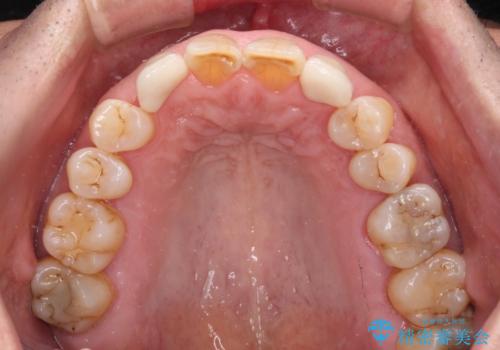

上顎の矮小歯は隙間が多く、歯軸の傾斜も大きかったため、部分矯正により補綴治療前に歯の位置を整えることとしました。

下顎の乳歯は支台歯として機能することは困難と思われたので、事前に抜歯をし、上顎の矯正治療終了のタイミングに合わせて、セラミックブリッジにて補綴治療することとしました。

前歯部はディープバイトという、上顎前歯が下顎前歯に深く覆い被さる咬合であったので、理想的には全顎矯正が必要となりますが、今回は患者希望により前歯部のみの部分矯正で対応しました。そのため下顎犬歯の神経を取り除くことになってしまったのは心残りであります。